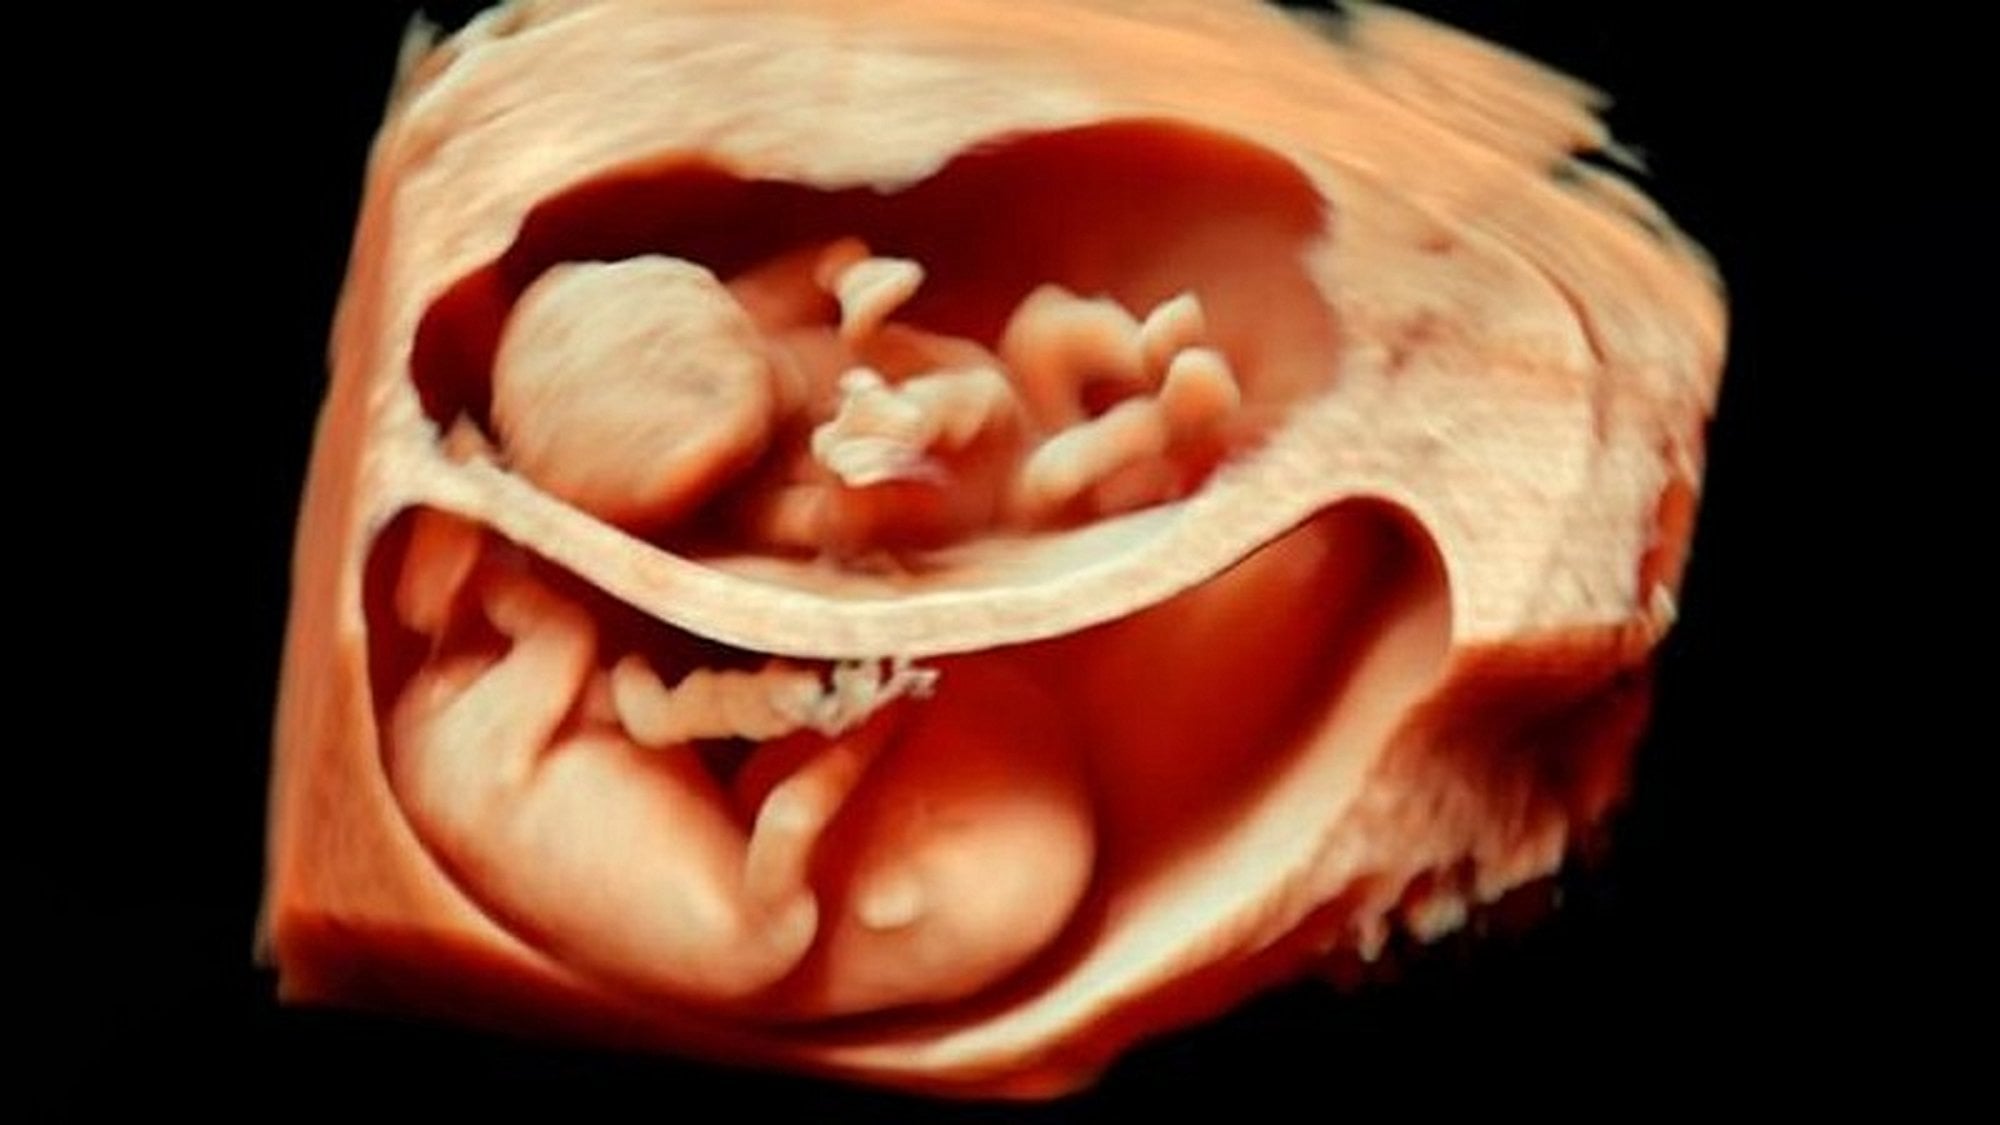

Bu görüntüleme tekniği sayesinde, artık renkli ve çok daha net sonuçlara ulaşabiliyoruz. Bu görseller, bunun en net ispatlarından biri. Ana karnındaki ikizleri çok detaylı bir şekilde görüntülemek artık mümkün. Hem de o, uzaktan odaklanılmış bir kare. Aşağıdakiler, ne demek istediğimizi daha net anlatacaktır:

3D ultrasonlarda, birden fazla açıdan 2 boyutlu görüntüler çekiliyor ve sonrasında bilgisayar yardımıyla 3 boyutlu bir görsele dönüştürülüyor. Bu sayede bebeğinizin sadece bir kesidini değil, 3 boyutlu bir görüntüsünü elde etmeniz mümkün oluyor.